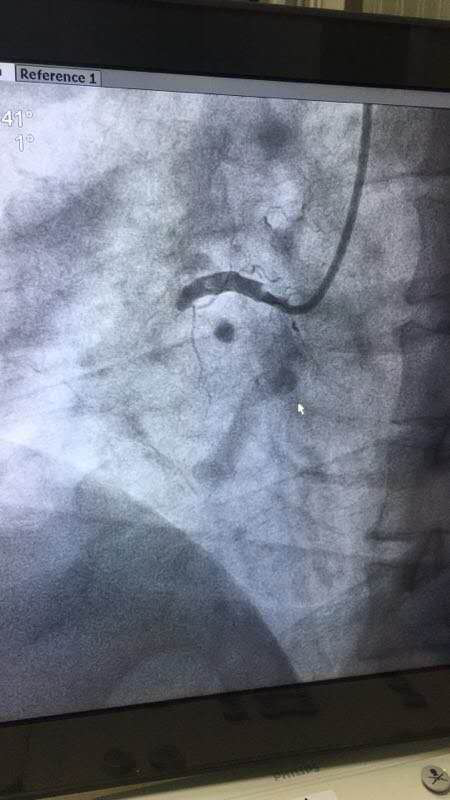

给患者植入支架术后